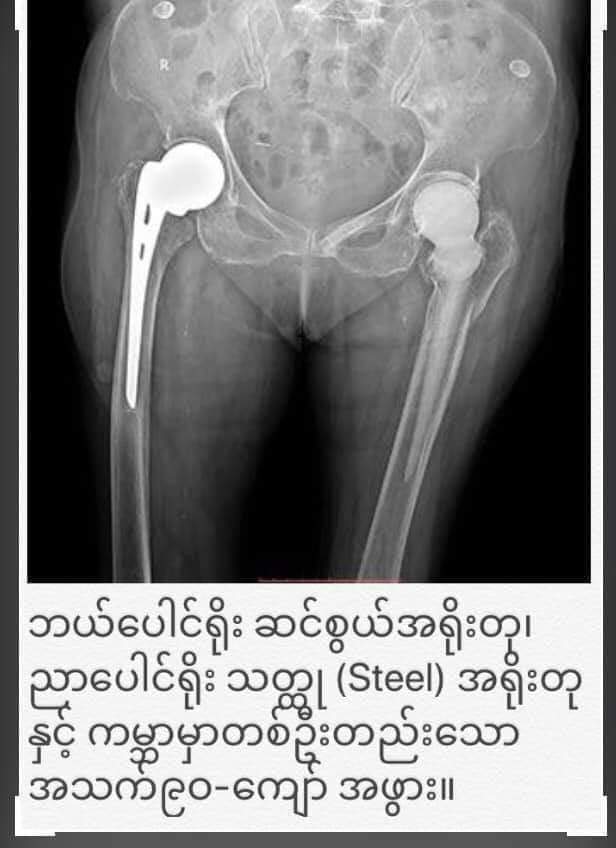

၂ဝ၁၉-နိုဝင်ဘာလမှာ လေ့လာခဲ့တဲ့ စစ်တမ်းအရ ၂ဝ၁၉-ခုနှစ်အထိ အသက်ရှင်လျက်ရှိတဲ့ ဆင်စွယ်အစားထိုးကုသမှု ခံယူထားသူ၃-ဦး တွေ့ရပါတယ်။အသက် ၆၄-နှစ်ရှိ ဒေါ်သန်းဌေး (အသက်၁၃-နှစ်မှာခွဲစိတ်ခဲ့)၊ အသက်၆၇-နှစ်ရှိ ဒေါ်အမာတင် (အသက်၁၅-နှစ်မှာခွဲစိတ်ခဲ့) နဲ့ ဒေါ်သန်းသန်း အသက်၉ဝ-ပါ။ ဒေါ်သန်းသန်းဟာ စိတ်ဝင်စားဖွယ်ကောင်းတဲ့ လူနာတစ်ဦးပါ။ သူ့အသက်၇ဝ-ခန့် ၁၉၉၅-ခုနှစ်မှာ ဘယ်ဘက်ပေါင်ရိုးကျိုးလို့ ဆရာဦးစံဘော်ရဲ့ တပည့် ပါမောက္ခဦးမိတ် က ဆင်စွယ်နဲ့အစားထိုး ခွဲစိတ်ကုသခဲ့ပါတယ်။ ၂ဝ၁၈-ခုနှစ်မှာ ညာဘက်ပေါင်ရိုးကျိုးလို့ ပါမောက္ခဦးစိန်လှဦးက စတီးရိုး (Austin Moore Prosthesis) နဲ့အစားထိုး ခွဲစိတ်ပေးခဲ့ပါတယ်။ ဒေါ်သန်းသန်းဟာ ဘယ်ပေါင်ရိုး ဆင်စွယ်အရိုးတု၊ ညာပေါင်ရိုး စတီးအရိုးတုနဲ့ ကမ္ဘာပေါ်မှာ တစ်ဦးတည်းသော အသက်၉ဝ-ကျော် အမျိုးသမီးကြီးအဖြစ် မှတ်တမ်းဝင်ပါတယ်။